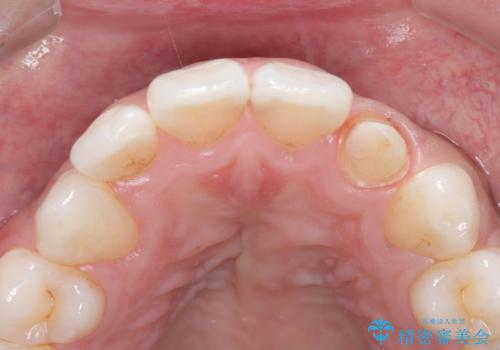

- 「前歯の歯の色が気になる」を主訴に来院された患者さんです。歯の大部分がプラスチックの材料で治療されていました。そこが劣化し変色していたためオールセラミッククラウンで治療を行いました。前歯の色を全体的に白くするために当院でオフィスホワイトニングも行いました。

左上2番の大部分がプラスチックの材料で治療されていました。そのプラスチックの材料が劣化して変色し虫歯になっている状態でした。なので古いプラスチックの材料を全て除去し、その下の虫歯を取った後、オールセラミッククラウンで治療を行いました。オールセラミッククラウンを装着する前に当院にてホワイトニングを行いました。